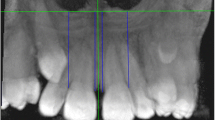

Firstly, a 3D skull was obtained from reoriented CBCT images by threshold segmentation using ProPlan CMF 1.4 software (Materialise, Leuven, Belgium) [15]. Secondly, to separate the maxilla from the 3D skull, the landmarks of maxillary boundaries were defined as follows: the lowest point on the temporal side of the maxillary anterior alveolar ridge on the median was U1’; the lowest points on the middle of the temporal alveolar ridge of the left and right maxillary first molar were U6L’ and U6R’, respectively; the farthest and lowest points on the temporal alveolar ridge of the left and right maxillary second molar were U7L’ and U7R’, respectively. According to these landmarks, the boundaries of the maxilla were assessed as below: the lowermost horizontal plane was through U1’, U6L’, and U6R’; the foremost coronal plane was through U1’; the backmost coronal plane was through U7L’or U7R’; and the uppermost horizontal plane was through ANS (Fig. 2a). The 3D object of maxilla was segmented and exported as standard tessellation language (STL) format document (Fig. 2b). Finally, Geomagic Studio 11.0 software (Raindrop Geomagic, Inc., NC, USA) was used to transfer reconstructed 3D object of the maxilla into 3D palatal morphology. In order to separate the palate from the maxilla, the lowermost horizontal plane and the backmost coronal plane of the maxilla were chosen through the method of plane cutting. After the separation, the palate was selected to create a bounded component followed by filling the boundary hole to obtain a 3D closed figure of the palate (Fig. 3) [12].

The 3D maxilla obtained from the 3D skull. a, the boundaries of the maxilla. 1, The lowermost horizontal plane was through U1’, U6L’, and U6R’; 2, the foremost coronal plane was through U1’; 3, the backmost coronal plane was through U7L’or U7R’; 4, the uppermost horizontal plane was through ANS. b, The 3D objects of maxilla. 1, Upwards view; 2, front view; 3, lateral view; 4, the 3D maxilla in the 3D skull